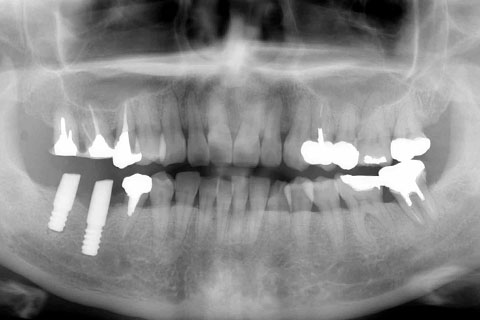

• 症例2

治療前

インプラント埋入時

治療後

年齢・性別

57歳男性

治療期間

3ヶ月

抜歯

なし

治療費

154万円

備考

左上5.6.7 及び左下6.7欠損

治療内容

左上5.6.7と左下6.7欠損部にインプラント埋入

施術の副作用(リスク)

オペによる知覚障害。インプラントによる歯肉炎。インプラント脱落。